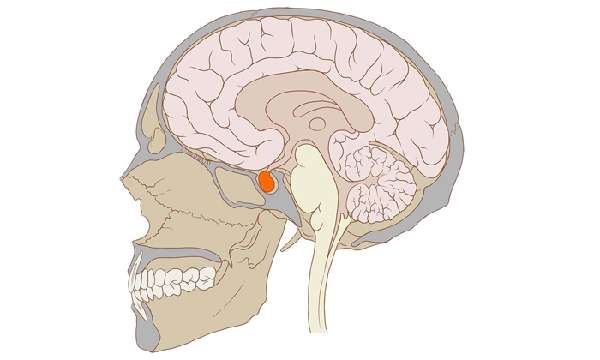

Детальна етіологія амнезії і її різновидів все ще не встановлена. Імовірно органічні ушкодження полягають в повній дисфункції ряду церебральних нейронів і розриві їх межнейрональних зв’язків в лімбічної системі, яка реєструє, кодує, а потім відтворює наявну інформацію.

В цьому випадку в зв’язку з масовою загибеллю відповідають за її зберігання структурних елементів допускається необоротна втрата відомостей про минулі події.